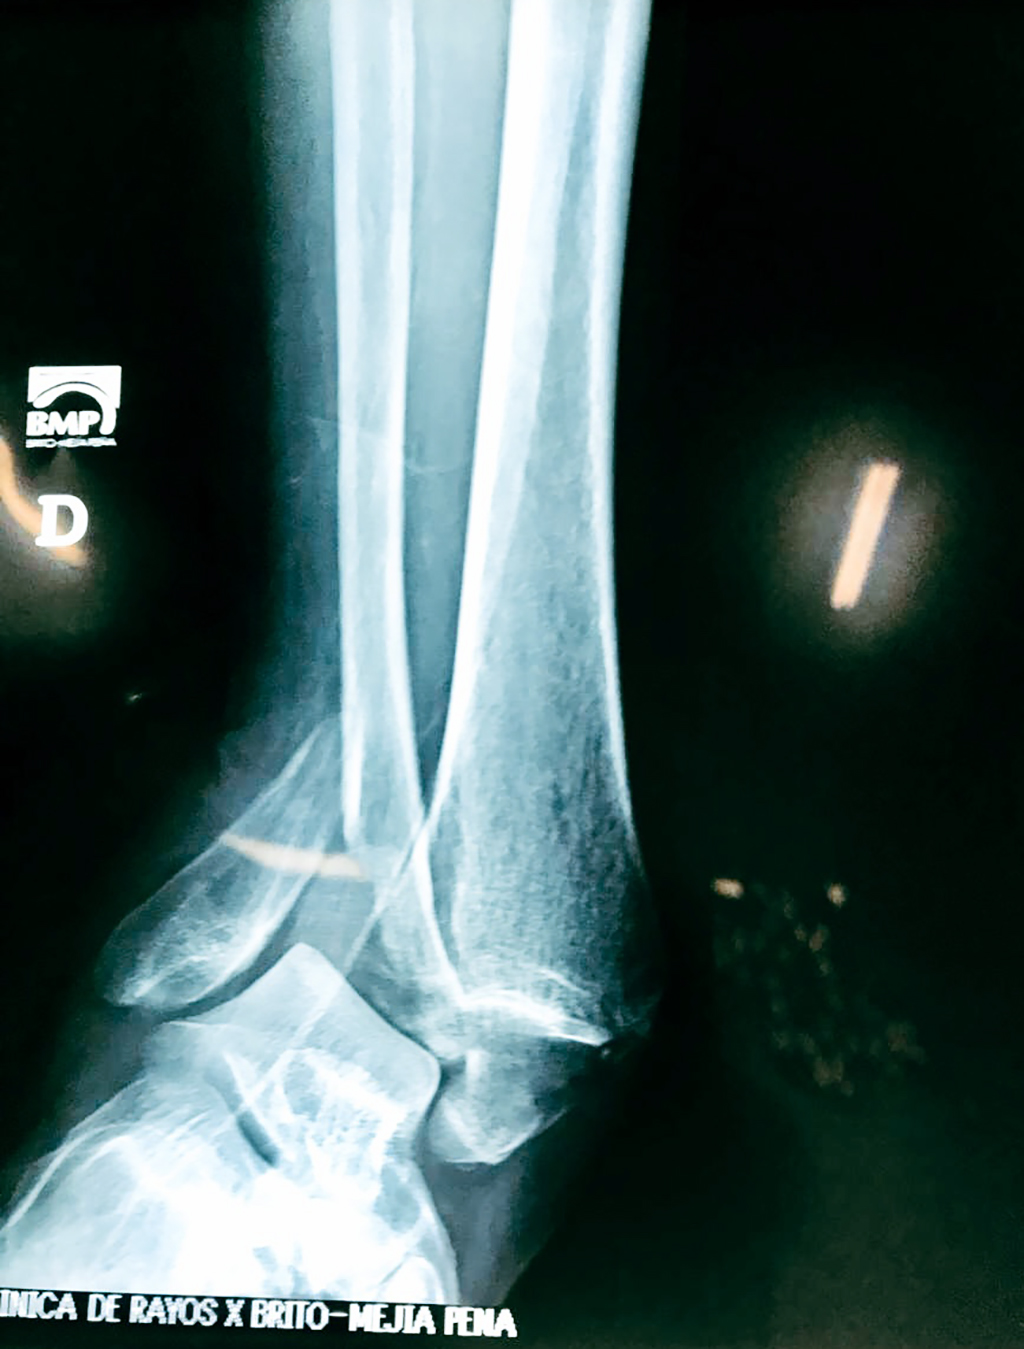

Una fractura de tobillo es la rotura de uno o más de los huesos del tobillo. Estas fracturas pueden ser:

Algunas fracturas de tobillo pueden requerir cirugía si:

- Los extremos de los huesos están desalineados entre sí (desplazados).

- La fractura se extiende hasta la articulación del tobillo (fractura intra-articular).

- Los tendones o ligamentos (tejidos que sujetan los músculos y los huesos entre sí) están rotos.

- El médico cree que sus huesos probablemente no sanen apropiadamente sin cirugía.

- El médico considera que la cirugía puede permitirle una recuperación más rápida y confiable.

- En los niños, la fractura involucra la parte del hueso del tobillo donde el hueso está creciendo.

Cuando se necesita cirugía, es probable que esta implique el uso de clavijas de metal, tornillos o placas para sostener los huesos en su lugar mientras la fractura se consolida. Los elementos de soporte pueden ser temporales o permanentes.